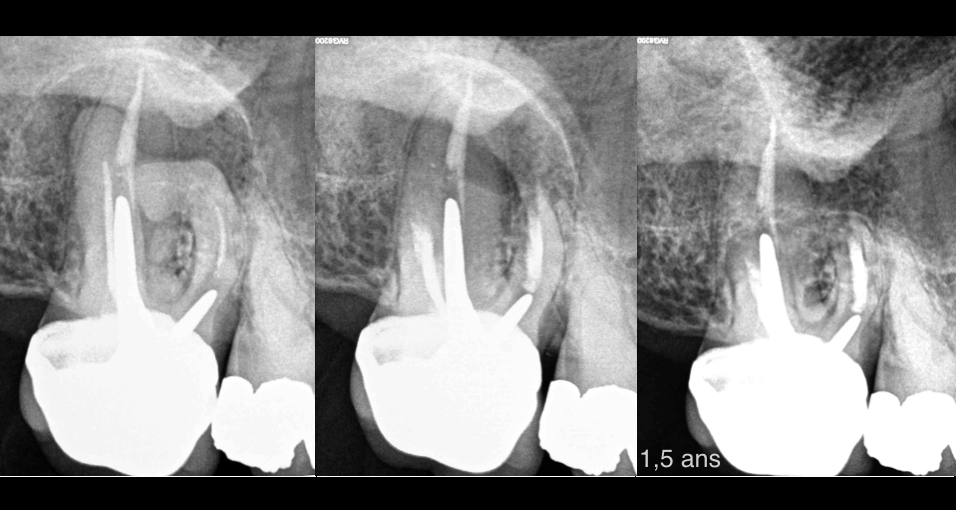

🔍 Une belle indication de chirurgie endodontique pour cette 17 !

➡️ Courbure très prononcée du canal MV

➡️ Fausse route du précédent traitement canalaire